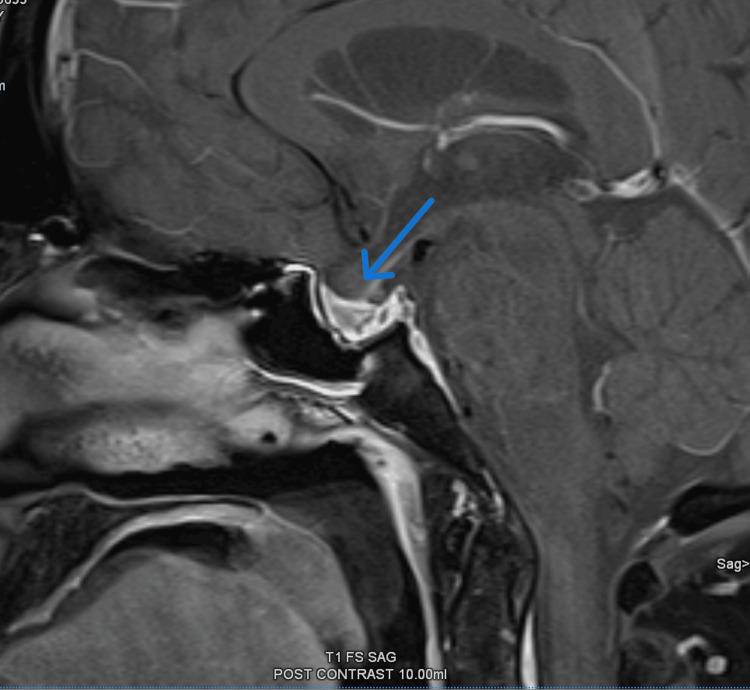

Pituitary apoplexy is a life-threatening condition caused by a rapid expansion of the pituitary tumor due to hemorrhage or infarction. It usually presents with acute onset severe headache and can also be associated with visual field defects and ophthalmoplegia. Similarly, ocular myasthenia gravis, which is an autoimmune condition causing muscle fatiguability, also presents with ophthalmoplegia, commonly ptosis and diplopia. A 53-year-old male patient with a past history of adrenal insufficiency presented with acute onset headache. On examination, he had bilateral asymmetrical partial ptosis and left-side medial rectus palsy with mild fatiguability. He had normal visual fields and sparing of the pupils. Acetylcholine receptor antibodies were positive but failed to demonstrate a decremental response in nerve conduction studies. The patient was started on neostigmine on clinical suspicion of ocular myasthenia gravis. A magnetic resonance imaging (MRI) scan of the brain was arranged to look for any intracranial pathology for persistent headache and it revealed evidence of pituitary apoplexy with compression of optic chiasm and partial obliteration of bilateral cavernous sinuses. In view of MRI findings, a diagnosis of pituitary apoplexy with third cranial nerve involvement was considered the first differential diagnosis, and the patient was started on replacement hormones while temporarily withholding neostigmine. Following multidisciplinary input, it was decided to manage the patient conservatively. A repeat MRI brain was planned to assess the evolution which revealed resolution of pituitary apoplexy. Despite this, the patient continued to have ophthalmoplegia and fatigable partial ptosis. Pyridostigmine was restarted following which the patient fully recovered, confirming the diagnosis of ocular myasthenia gravis presenting concomitantly with pituitary apoplexy.

垂体卒中是一种由垂体肿瘤因出血或梗死而迅速扩大所导致的危及生命的病症。它通常急性起病,表现为严重头痛,还可能伴有视野缺损和眼肌麻痹。同样,眼肌型重症肌无力是一种导致肌肉易疲劳的自身免疫性疾病,也表现为眼肌麻痹,常见上睑下垂和复视。一名有肾上腺功能不全病史的53岁男性患者出现急性头痛。检查发现,他有双侧不对称性部分上睑下垂和左侧内直肌麻痹,伴有轻度易疲劳性。他视野正常,瞳孔未受累。乙酰胆碱受体抗体呈阳性,但神经传导研究未显示递减反应。临床怀疑为眼肌型重症肌无力,遂开始给予患者新斯的明治疗。安排了脑部磁共振成像(MRI)扫描以查找持续性头痛的任何颅内病变,结果显示有垂体卒中的证据,视交叉受压,双侧海绵窦部分闭塞。鉴于MRI检查结果,首先考虑诊断为累及第三脑神经的垂体卒中,开始给予患者补充激素,同时暂时停用新斯的明。经过多学科会诊后,决定对患者进行保守治疗。计划再次进行脑部MRI检查以评估病情演变,结果显示垂体卒中已消退。尽管如此,患者仍有眼肌麻痹和可疲劳性部分上睑下垂。重新开始给予吡啶斯的明治疗后,患者完全康复,证实诊断为眼肌型重症肌无力与垂体卒中同时存在。